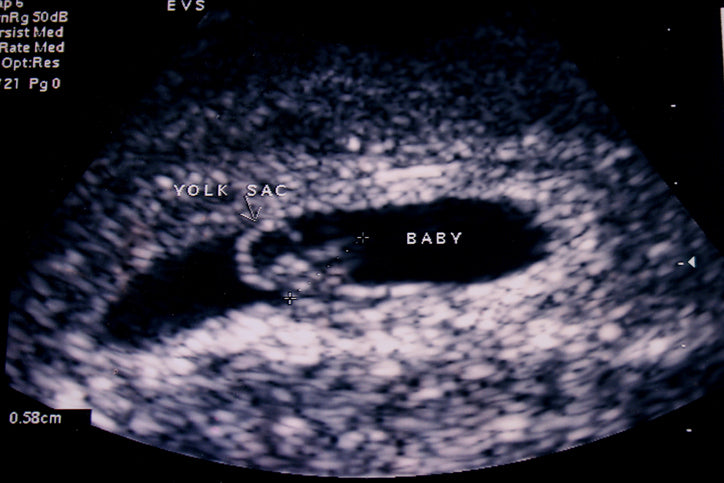

A dating scan is an ultrasound performed to learn the age of the pregnancy. If you or your doctor/midwife is unsure of the date of your last menstrual cycle, if you have had any bleeding, or you are unsure of when you conceived, you will receive a dating sonogram.

This ultrasound will show you exactly how far along you are, and will show you your baby as early as 4 weeks and 3 days along! (But don’t panic because some pregnancies cannot be seen until 5 weeks.)

You will see the beginnings of a gestational sac, but no heartbeat or further fetal development yet at this stage. An embryo and fetal heartbeat can be detected as early as 6 weeks and 3 days but may not be picked up until further along.

At 5.5 weeks gestation, a tiny sac can be seen in the uterus, but the baby and heartbeat may not be detected yet. 5.5 weeks gestation means five and a half weeks from the first day of the last menstrual period, which is usually about 3.5 weeks from the date of conception. (confusing, isn’t it?)